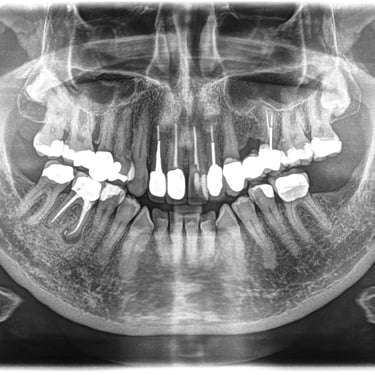

Returning the next day, we picked up Greg’s mouth guard and Dr. Maksuti got me back in the chair for a deeper examination and procedural discussion. He would need x-rays to confirm the process. There is an office a block down the street that does the x-rays, so off we went with the prescription. Staff in the Grafi Dentare office were kind and expedient as they took my personal information and completed a full-face dental x-ray. Cost of the X-ray? 2,000 Leke ($24.17) and they sent the scan to the dentist and to my phone for my permanent record keeping.

With x-ray in hand, Dr. Maksuti examined it closely. He showed his concern to Greg and me. Deep in the roots on the right-hand side was an infection. Nodding, I knew of this issue. It was a dormant infection that my endodontist has been monitoring for 4 years. It flares up under extreme periods of stress (like when I was working), but it lies dormant mostly. Greg, a registered nurse, had not seen this scan before and was concerned. The three of us deliberated with Greg and I doing most of the talking while asking questions from the dentist. Being retired now, I was on state insurance in the USA, so who knows when they could fit me in for an appointment, besides, we had MONTHS to go before we even returned to the states. What happens if it flares up again while we’re traveling? Then we’d have to face emergency care, which can cause more stress. And, if we had the dental emergency, would it be in a language we could understand? Looking both men in the eye, I realized removing the tooth now and treating the infection made the most sense. My endodontist had planned the same “treatment” if it flared up again anyway. I made an appointment for Monday, three days away.

With an aching jaw I wanted to go home, but Dr. Maksuti needed one more x-ray to ensure he had indeed extracted every tiny piece of the tooth. So, we schlumped back over to the office and got another full-face x-ray for another 2,000 Leke ($24.17). Without patience, Greg held that x-ray to the sun and looked carefully at it. He spied what might be another piece, so I was ushered back to the dental office. With another client waiting in reception, Dr. Maksuti looked over the film and agreed with Greg, there was another piece of the tooth. I sighed. The dentist sighed. The assistant/receptionist sighed. And I trudged back to the chair that had been cleaned in my absence.